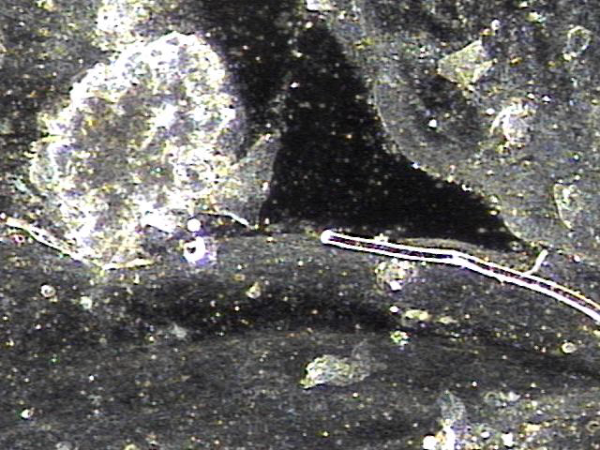

지속적인 전립선의 표적 치료후 치료된 사정관과 정관 그리고 정낭등에 막혀 있던 상피세포 덩어리의 현미경학적 자료입니다.

This is a microscopic image of epithelial cell clusters that had been blocking the ejaculatory ducts, vas deferens, and seminal vesicles, which were cleared following continuous targeted prostate treatment.